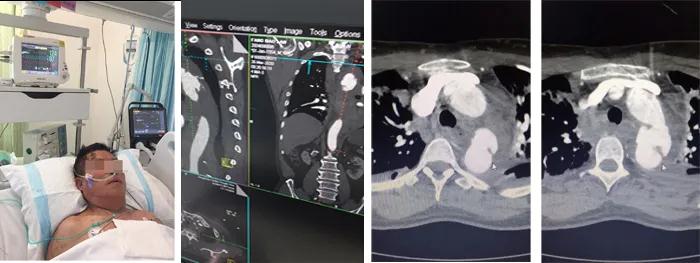

3月26日,66歲的房先生因為車禍事故導致全身多發(fā)骨折,生命體征不穩(wěn)定,在當?shù)蒯t(yī)院診斷為多發(fā)肋骨骨折、雙肺挫傷、左側(cè)血胸、創(chuàng)傷性失血性休克,CT影像檢查發(fā)現(xiàn)可疑主動脈夾層。因病情嚴重緊急,迅速轉(zhuǎn)運至我院急診科,經(jīng)創(chuàng)傷救治綠色通道CT室急診行主動脈CTA檢查,示降主動脈夾層破裂,縱膈及左側(cè)胸腔大量積血,右側(cè)血氣胸。急診收入我院心臟大血管外科。

入院后,患者呼吸微弱,血壓僅65/40mmHg,血常規(guī)示:血紅蛋白由130下降至49g/L。主動脈CTA確診患者為主動脈夾層破裂,主動脈內(nèi)膜撕裂形成假性動脈瘤,胸腔和縱膈出現(xiàn)大量積血。柴召強醫(yī)師考慮患者病情患者危重,休克狀態(tài),隨時有死亡可能。向醫(yī)務部周永勤主任匯報,并向患者家屬講明病情,決定急診行主動脈腔內(nèi)覆膜支架植入腔內(nèi)修復術(shù)。